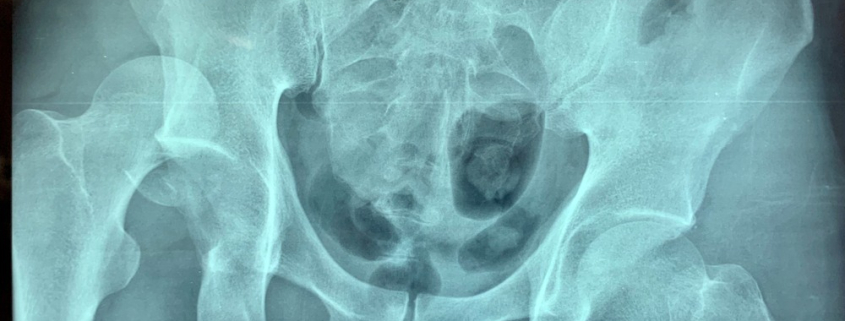

L’articolazione dell’anca, una delle più importanti e mobili del nostro corpo (è quella che ci permette di camminare), è costituita dal femore (l’osso della coscia) e dall’osso iliaco (che fa parte del bacino). L’estremità prossimale del femore (detta testa del femore), di forma convessa, trova alloggio in una cavità dell’osso iliaco, detta acetabolo.

Quando, a causa di un evento traumatico, la testa del femore fuoriesce dall’acetabolo, cioè dal suo alloggio naturale, si avrà una lussazione dell’anca, evento estremamente doloroso e invalidante.

La lussazione dell’anca può essere incompleta, quando il contatto fra le ossa che costituiscono l’articolazione viene in parte conservato, o completa, quando il contatto fra le ossa viene a mancare completamente.

Nella stragrande maggioranza dei casi, questo tipo di infortuni causa una lussazione posteriore: in pratica la testa del femore fuoriesce dall’acetabolo portandosi indietro e leggermente in alto rispetto a quest’ultimo. Purtroppo, non di rado questo infortunio è accompagnato dalla frattura dell’acetabolo e/o della testa del femore.

La diagnosi di lussazione d’anca è piuttosto semplice: si basa su un esame obiettivo, sui sintomi del paziente e su test radiologici che, oltre a confermare la presenza della lussazione, servono a escludere danni più gravi come fratture, osteonecrosi (morte del tessuto osseo dovuto al ridotto apporto di sangue) e lesioni a tendini, muscoli e legamenti.